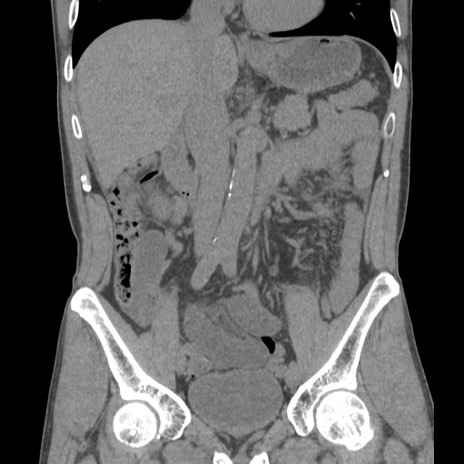

症例56 CT(冠状断像)

横断像